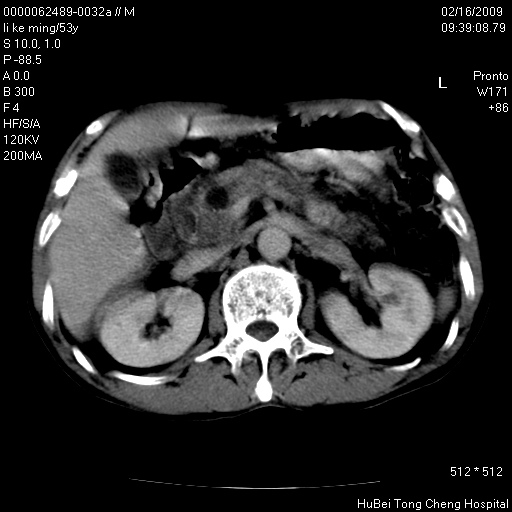

以下是引用dyqct在2009-2-16 16:58:00的发言:[br]胰头内斑点状及结节状高密度影是钙化灶还是其它?以往做过什么治疗?

以下是引用zsl6918在2009-2-17 8:48:00的发言:[br]符合胰头癌侵犯十二指肠。